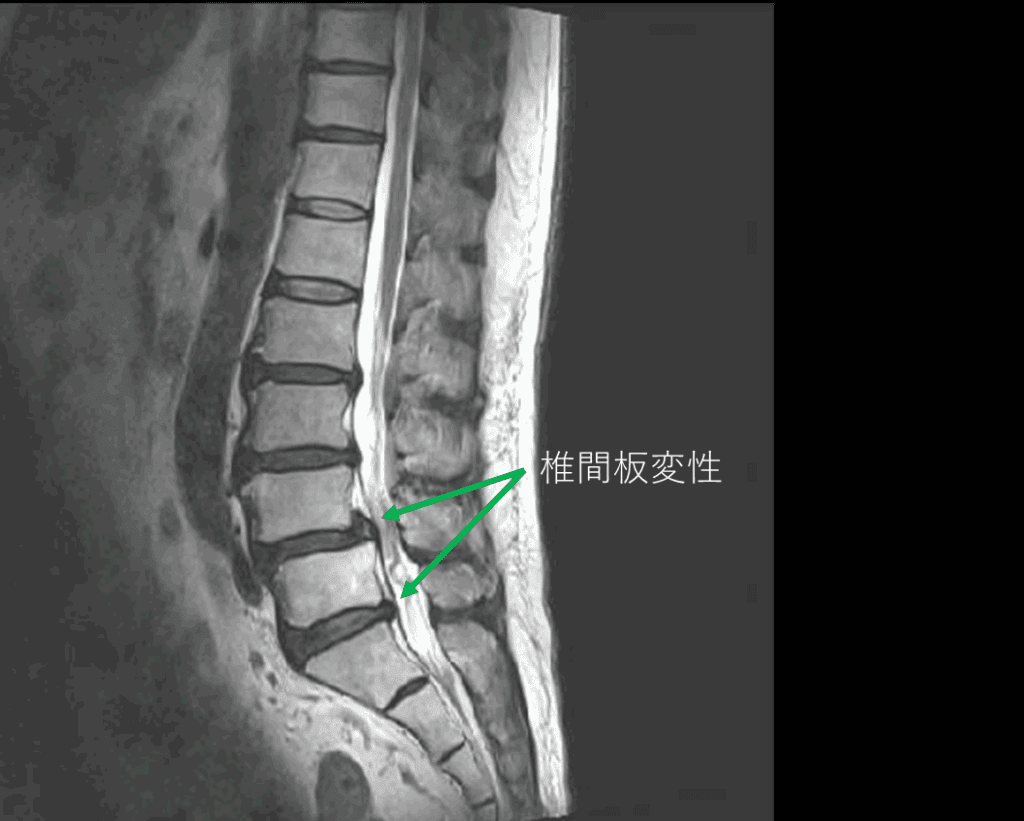

画像及び所見について

- L2/3,3/4,4/5,5/s-椎間板変性

- L4-前方すべり

以上の事が画像上認められます。

・L4/5,5/s-椎間板変性による椎間孔狭窄を認め、主症状の原因と考えられる。